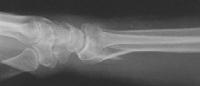

Clinical Example: Distraction plate fixation distal radius fracture

distal radius fracture

distraction plate